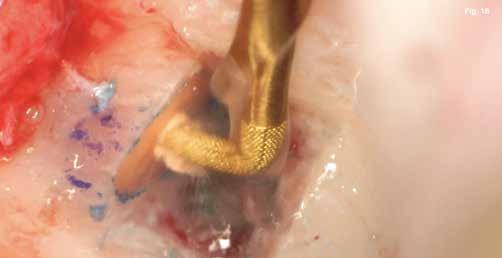

A szubmarginális teljes vastagságú lebenyt két felszabadító bemetszéssel végeztük egy 69-es számú, dupla lekerekített mikropengével (Swann–Morton) (6–7. ábra) A vestibularis csont ép volt, ezért csontablak-technikát alkalmaztunk és végeztünk (6–8. ábra) piezo készülékkel (Woodpecker DTE AI Surgery) és „US1, UC1” (Guilin Woodpecker Medical Instrument Co., LTD) hegyekkel. A blokkot az intraoperatív szakaszok alatt sóoldatban tartot-

tuk. Az apikális reszekciót (8. ábra) az „UC1” (Guilin Woodpecker Medical Instrument Co., LTD) segítségével végeztük el, és a gyökeret egy 3 mm-es „MM4” (Hu-Friedy Manufacturing Co. LLC) kerek tükörrel vizsgáltuk a VRF szempontjából (13. ábra). A gyökérvég polírozását (11. ábra) az „UL4” (Guilin Woodpecker Medical Instrument Co., LTD) segítségével végeztük. A csontos kripta küretizálása kézi küretezéssel történt, de a csontos kriptában lévő további hámbélés eltávolításával a gyógyulási folyamat felgyorsítása érdekében piezo „UL3” (Guilin Woodpecker Medical Instrument Co., LTD) piezo hegyet is használtunk (9–10. ábra). A három mm-es retropreparációt (14–17. ábra) a „JT2SA” hegy (B&L Biotech) segítségével végeztük el. A retropreparációt ismét ellenőriztük a guttapercha maradványok tekintetében, leöblítettük és papírhegyekkel meg-